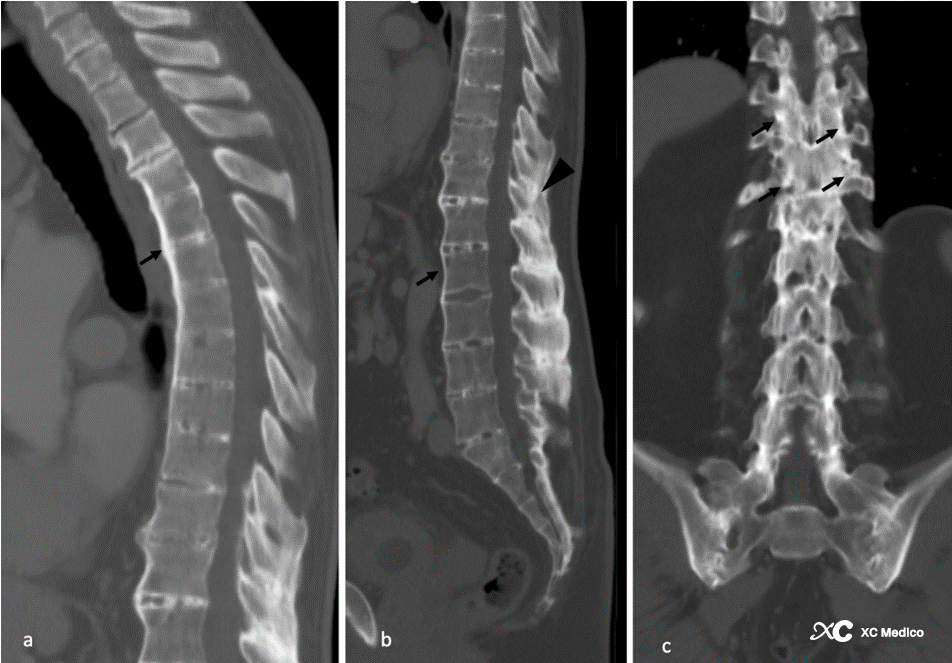

Примечание: пациент с анкилозирующим спондилитом, 44-летний мужчина с хронической болью в пояснице и ограниченным диапазоном движений. Сагиттальная КТ из (а) грудного и (б) поясничного отдела позвоночника показывает диффузный связочный синдесмоз вдоль передней продольной связки (стрелки). Существует также окостенение и слияние поясничных междувных связок (отображаемые стрелки). (C) Корональное изображение на уровне поясничного отдела позвоночника показывает слияние задних элементов и суставных синовиальных суставов (стрелки).